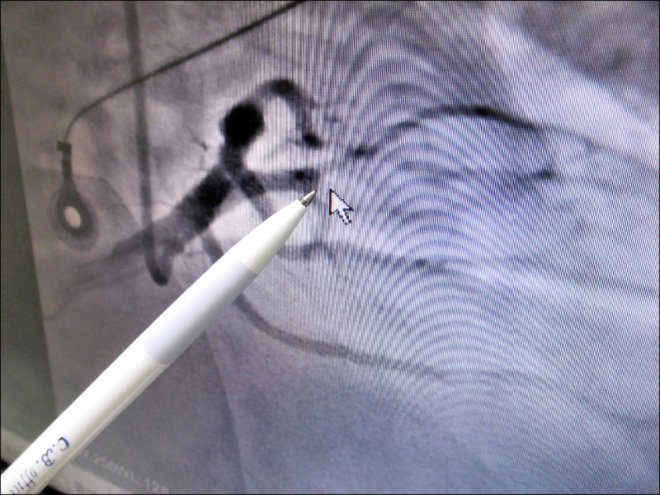

經過檢查後發現是急性心肌梗塞,情況已經糟到「2條心臟血管全塞住」,需要緊急插管救治,跟時間賽跑動員護理師們幫忙做檢查、抽血輸血打藥,急忙做手術後才救回一命,慶幸的是,2週後他的病況慢慢恢復,轉往普通病房,心中對妻子深夜追劇充滿感激,再晚一步真的神仙也難救啊!